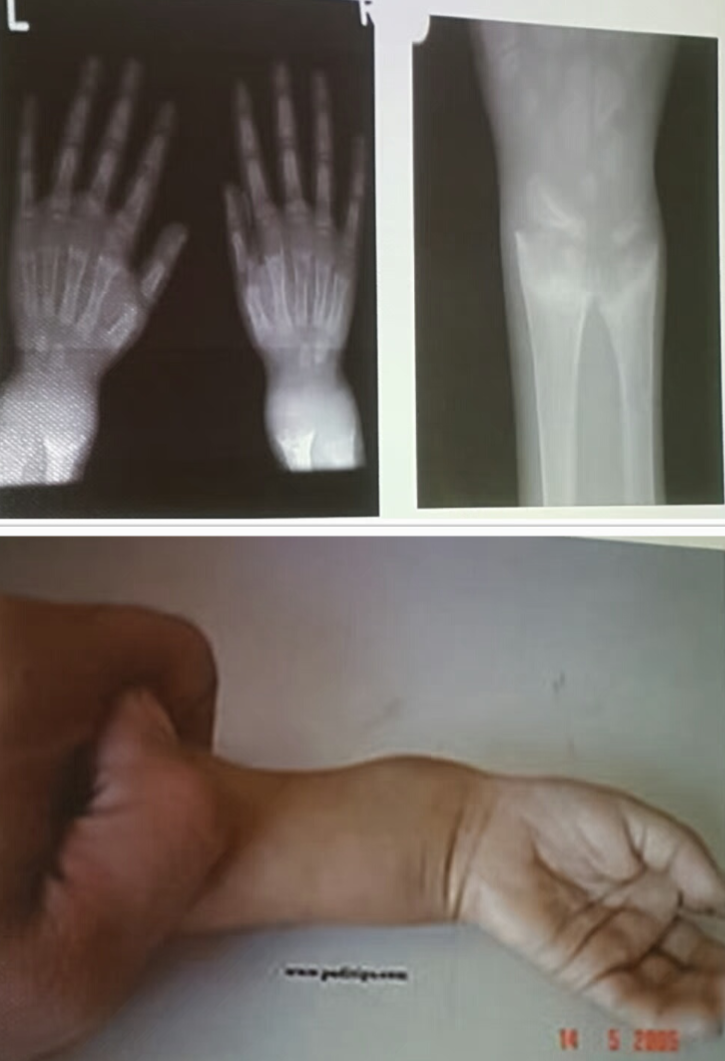

The bone age of this boy is 30 month (2y 6 month), but the chronological age is 5 years. give 2 cause of delayed bone age? 1.Hypothyroidism 2.Constitutional growth delay

- In which kind of rickets this finding will appear? Vitamin D dependent type 2

- What is the most likely diagnosis? Pseudohypoparathyroidism showing shortened fourth metacarpals.